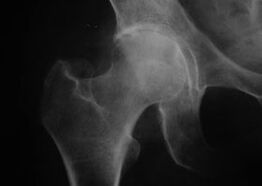

Aspect d'une articulation avec arthrose

Coxathrose, arthrose de l'articulation de la hanche

Avec cette maladie, on observe un tableau clinique classique de l'arthrose.

Le premier symptôme de la coxarthrose est une gêne au niveau de l'articulation de la hanche après une activité physique.

À mesure que la coxarthrose progresse, la douleur augmente, des raideurs et une mobilité limitée apparaissent.

Les patients atteints d'une forme grave de coxarthrose protègent le membre atteint, évitent de marcher dessus et, lorsqu'ils sont immobiles, choisissent les positions dans lesquelles la douleur est la moins perceptible.